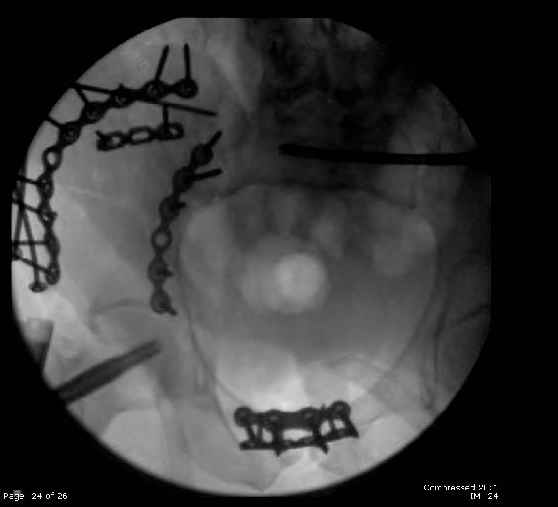

Here are the postop fluoros.

Fluoroed L SI joint and it seemed stable, but wide. So, applied c-clamp to try to squeeze down L SI joint (and note, on the last slide attached, that it's still wide), and got it closer. Single perc Iliosacral screw 40mm thread.

So, there I was with the aforementioned info on my mind, and my R iliac wing was a little malreduced. I think it's in residual extension and some external rotation, explaining the 5-6mm gap/step

on the posterior R iliac wing. (When I loooked at the inlet fluoro, the L obturator foramen was more visible than the R obt foramen, as was the R ischial spine) so it's not as stable as if it were

anatomic, despite all the metal. This came from hesitance to take down all the posterior paraspinals to really see the R posterior crest (where the malreduction is best seen on the iliac oblique view), and I could see the entire iliac fossa and most of the crest anyway.